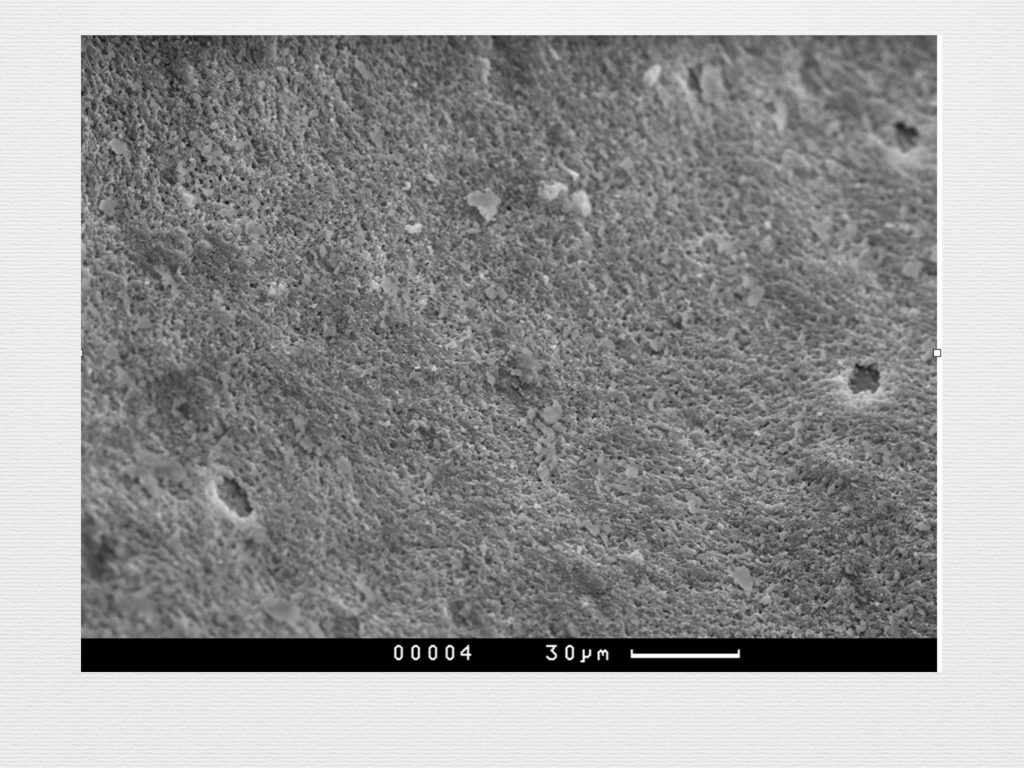

Принцип направленной костной регенерации. Костная регенерация под защитой мембраны Биоматрикс

Принцип направленной костной регенерации. Костная регенерация под защитой мембраны Биоматрикс

Принцип направленной костной регенерации. Костная регенерация под защитой мембраны Биоматрикс